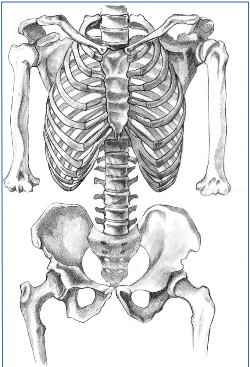

– Articular. En la osteopatía articular tratamos el aparato músculo – esquelético, donde vemos problemas relacionados de cervicales, dorsales, lumbares, sacro y cóccix.